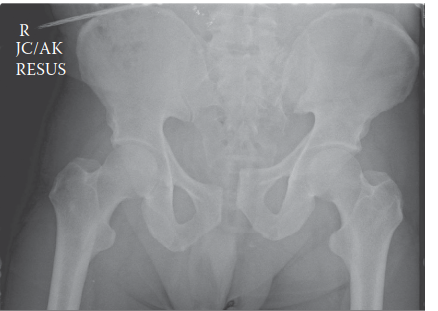

Radiographic evaluation began in the trauma bay with a portable anteroposterior radiograph of the pelvis and a portable chest radiograph. The AP pelvis radiograph revealed a catastrophic disruption of the pelvic ring. There was a pubic symphyseal diastasis measuring approximately 6 centimeters, complete disruption of the right sacroiliac joint with 3 centimeters of cephalad migration of the right hemipelvis, and widening of the left sacroiliac joint anteriorly.